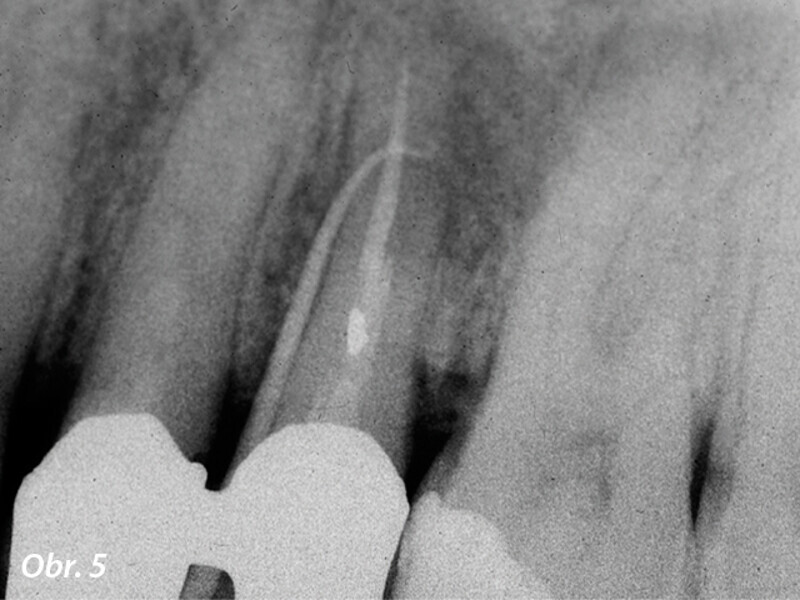

3D technologie v diagnostice a léčbě endodontických onemocnění